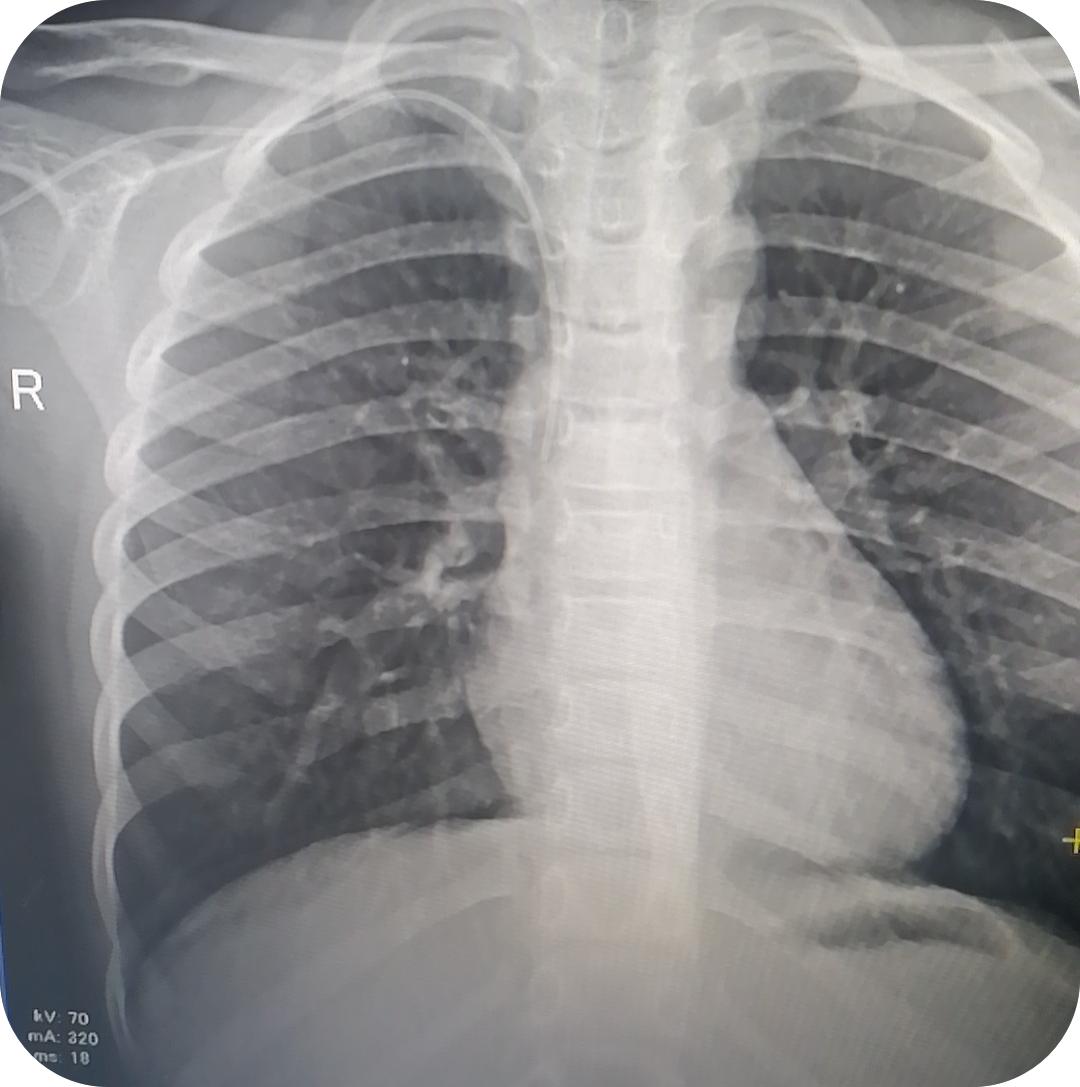

小月突然从口袋里摸出两枚粉色发卡:"护士姐姐,这个送你。"那是她用毛线装饰的蝴蝶结,在晨光里折射着彩虹。合影时,她嘴角梨涡盛着蜜糖般的笑意,此刻的病房,仿佛有无数透明的蝴蝶正从她眼底振翅飞出。最后,PICC导管尖端位于胸6椎体侧缘水平,非常完美。